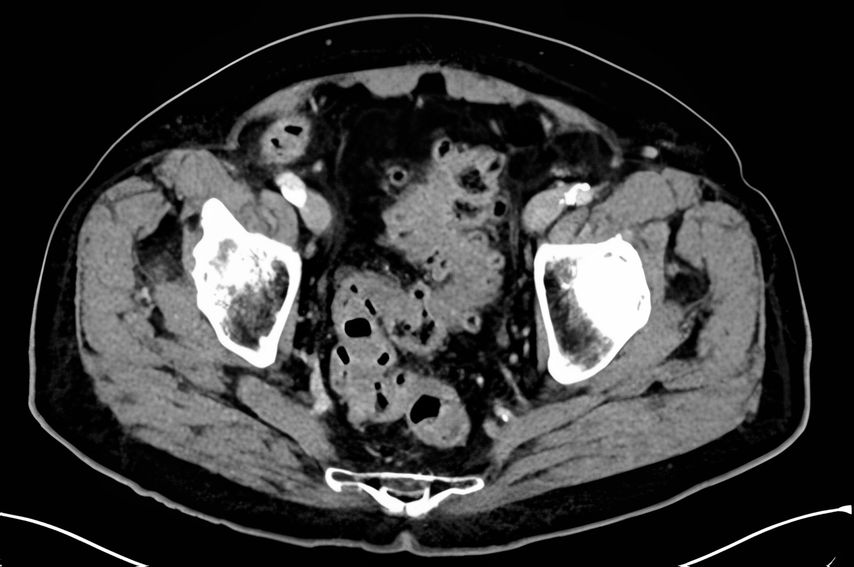

Während Patienten mit gedeckt perforierter Divertikulitis sich klinisch ähnlich präsentieren können wie Patienten mit unkomplizierten Divertikulitisverläufen vom Typ 1 (im Sinne einer Peridivertikulitis), zeigen sich die Entzündungsparameter hier in der Regel doch deutlicher erhöht. In der CT sehen wir einen Abszess, der je nach Grösse als Mikro- (<3cm) (Typ 2a) oder Makroabszess (>3cm) (Typ 2b) eingeteilt wird und für die weitere Therapie ausschlaggebend ist (Abb. 2). Das Rezidivrisiko weiterer Schübe korreliert zudem mit der Abszessgrösse.

Abb. 2: CT einer Divertikulitis CDD 2b mit interenterischem Makroabszess